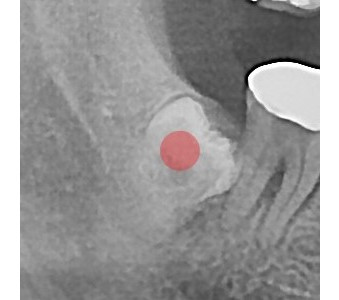

결과로 증명합니다.

국제모아치과의

실제 임상 증례